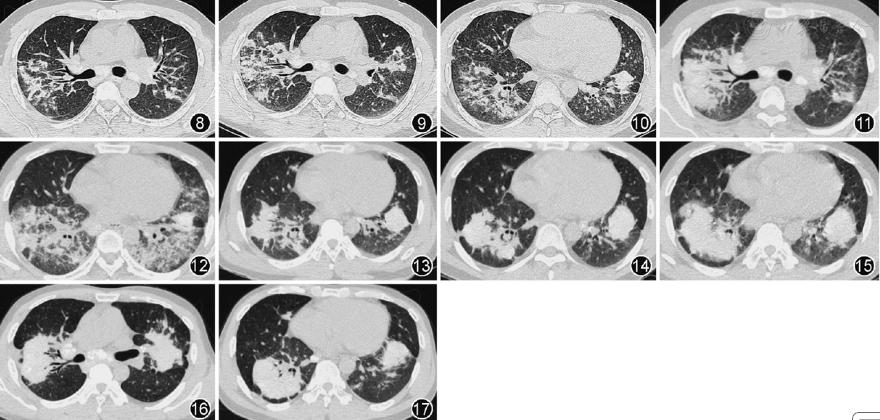

2013年9月至2016年9月,患者先后出现6次病情复发。归纳复发可能的诱因:1次为自行停用全身激素,2次为再次接触高浓度粉尘,1次为合并细菌感染,其余2次不明。症状多表现为咳嗽、咳痰及气喘,肺部查体多无明显异常体征;第5次复发因合并感染,出现发热、脓性痰,肺部可闻及湿性啰音。胸部CT(图8,图9,图10,图11,图12,图13):双肺可见片状、斑片状高密度影。病灶密度不均,由磨玻璃影到实变影不等,且多为二者混合性改变。病灶多累及整个叶、段,以双侧性及下叶分布为主,并沿支气管分布。无蜂窝肺样改变。病灶均对激素敏感,治疗1个月内多数病灶明显吸收。病情复发后,病灶呈游走性;病灶大小亦不完全相同,且病灶范围及大小与临床症状的严重程度有一定的相关性;随着复发次数的增加,病灶密度亦多呈逐渐增加,且病灶密度与激素治疗效果有一定相关性。除第5次复发因病情较重收住院加用抗菌素治疗外,其余均在门诊予全身激素加量处理后好转。

图8 第1次复发(2013年9月24日)胸部CT可见双上肺多发斑片状渗出实变影,以右上肺明显

图9第2次复发(2013年12月26日)胸部CT可见双上肺多发斑片状渗出实变影,以右上肺明显

图10 第3次复发(2014年7月2日)胸部CT可见双下肺多发斑片状渗出实变影,以右下肺明显

图11 第4次复发(2015年6月11日)胸部CT可见双上肺片状渗出实变影,以右上肺明显

图12第5次复发(2015年10月15日)胸部CT可见双下肺片状渗出实变影,双侧大致对称

图13 第6次复发(2016年9月22日)胸部CT可见双下肺片状实变影为主,右下肺混杂少量渗出性病灶

图14 胸部CT(2017年8月23日)可见双下肺片状实变影

图15胸部CT(2018年5月21日)可见双下肺片状实变影进一步增大

图16,17胸部CT(2019年5月6日)双上、下肺均可见巨块型矽结节

2016年9月22日患者再次复发,激素加量后症状缓解不明显,但因考虑到长期应用大剂量全身激素的副作用问题,故仍逐渐激素减量:泼尼松每1~2个月减2.5~5 mg。泼尼松减量至5~10 mg,1次/d时,患者出现咳嗽、咳痰及气喘加剧,短期激素加量(5~10 mg,1次/d),症状可好转,但无法完全停药。近3年来激素治疗量维持在5~15 mg,1次/d,时有咳嗽,痰少,活动后气喘渐明显,无法耐受体力活动,基本丧失劳动能力。复查肺功能(2019年5月)提示重度混合性通气功能障碍,肺部CT(2017年8月23日、2018年5月21日、2019年5月6日)示双肺多发高密度团块影,边界清,且缓慢进展(图14,图15,图16,图17)。